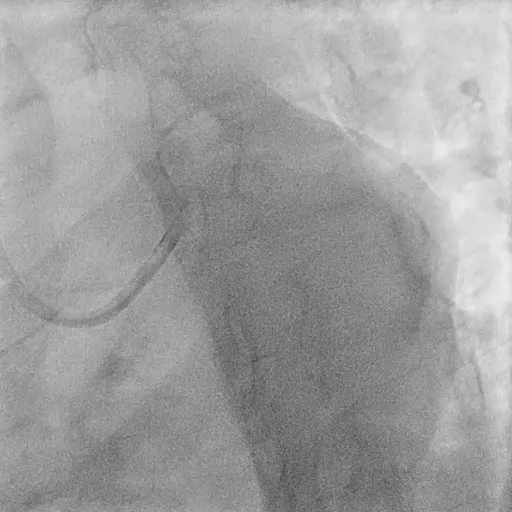

LCX Assessment

Rewiring into LCX

FFR at LCX: negative (0.93) → no PCI required